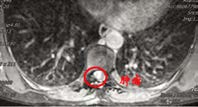

患者李女士(化名)来自西北少数民族地区,罹患胸段椎管内脊膜瘤,此前已在当地医院历经两次手术。近日,患她再次出现行走困难、疼痛难以平卧以及大小便费力,偶有失禁等症。患者首先回到最初就诊的省级医院,胸椎MRI示肿瘤再度复发,鉴于再次手术的难度和风险过高而被建议转院治疗。

几经辗转,患者来到我院神经外科就诊。郭振宇副主任医师接诊后,详细了解病情,发现“因多次手术,造成肿瘤与神经组织粘连严重,并且椎管腔内外解剖结构不清,再次手术患者瘫痪风险很高,并有可能大小便失禁”。